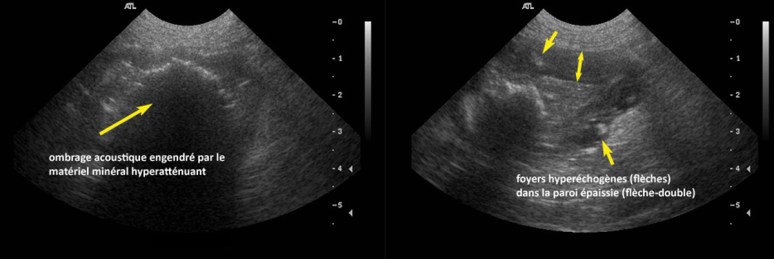

D’abord, une sonde a été glissée dans le colon pour en déterminer la localisation (flèches) et vérifier que les structures minérales étaient dans un segment du petit intestin. Une écho a aussi été faite, puis un CT. Puis, le chien a été envoyé en chirurgie (cliquer sur les images pour obtenir plus de détail).

Après excision de la paroi anormale et analyse histologique, voici le verdict: adénocarcinome mucineux kystique intestinale !